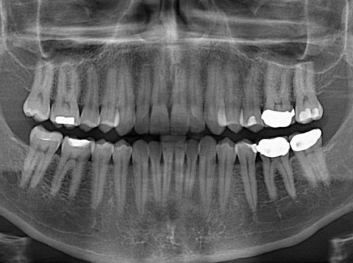

哈佛大學:新型生物材料讓牙齒再生

損壞的牙齒如何自我修復?近日,來自哈佛大學和諾丁漢大學的研究人員研發(fā)了能夠刺激牙齒干細胞再生的新型生物材料,而這種新材料…